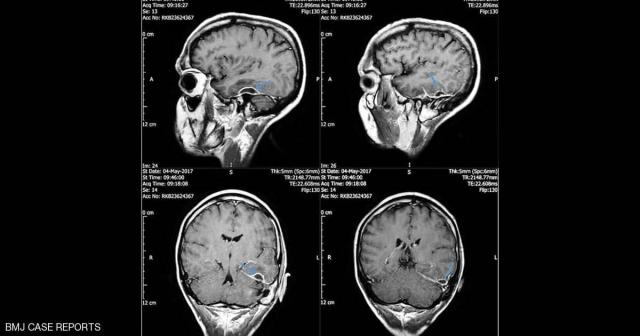

ففي المستشفى، اكتشف الأطباء أن المشكلة "باتت" أعمق مما كان يعتقد وأنها توجد داخل جمجمته.

وبحسب الأطباء فإن الالتهاب أصاب الخلايا داخل الجمجمة، ولم يصل إلى خلايا الدماغ.

وبعد 6 أيام من العلاج، لوحظ تحسن في حالته وتراجع الالتهاب في خلايا الجمجمة، وشفي تماما بعد 10 أسابيع.